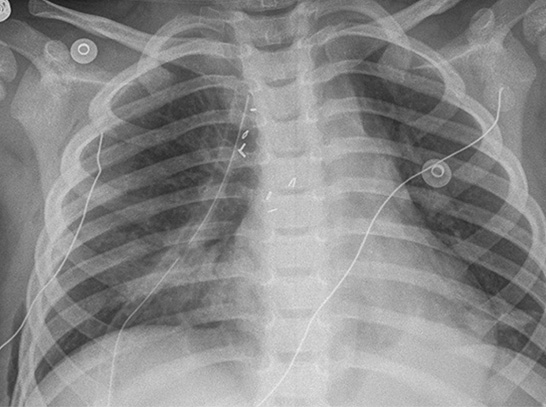

The doctor may perform Mediastinal surgery if there is a problem with one of the organs or tissue in the mediastinum. Organs in the mediastinum include the heart and its large vessels, trachea, esophagus, thymus gland, and lymph nodes. Mediastinal surgery may be done to remove tumors or abscesses, to remove the thymus gland, to treat infections, or to drain fluids.

The type of Mediastinal surgery done depends on the diagnosis or problem that is being surgically treated. An "open" procedure may be done where an incision is made on the chest. Sometimes, minimally-invasive surgery may be done through a scope, reducing the incision size and the recovery time. Resection of large mediastinal masses or tumors may require an approach through a large incision in the chest or by dividing the breast bone (sternotomy), or by dividing the ribs (thoracotomy).